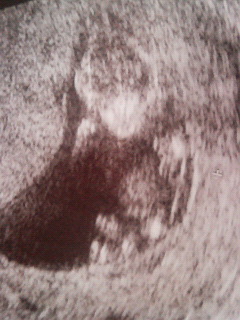

妊娠4ヶ月

赤ちゃんは順調で5cmくらいかな?今日も動いていて可愛かったです。

エコーもやってもらえました(^_^)v赤ちゃんは元気に動いていて

背骨もはっきり見えました。大きくなってた♪